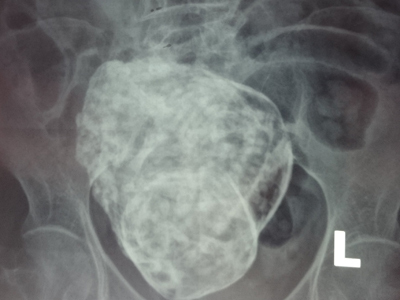

Trước đó, ngày 22/3, bà cụ đến Bệnh viện Đa khoa Cam Ranh khám vì cảm thấy đau vùng thắt lưng. Kết quả chụp phim X-quang cho thấy có hình hài bào thai nằm trong ổ bụng của cụ bà. Các bác sĩ dự đoán, bào thai này rất có thể đã hình thành cách đây gần 30 năm trước và nhận thấy đây là trường hợp hiếm gặp, rất hy hữu trong y khoa của thế giới, do vậy phải thận trọng, đảm bảo an toàn cho cụ bà khi can thiệp y khoa.

| Hình ảnh bào "thai đá" trong ổ bụng cụ bà 76 tuổi. |